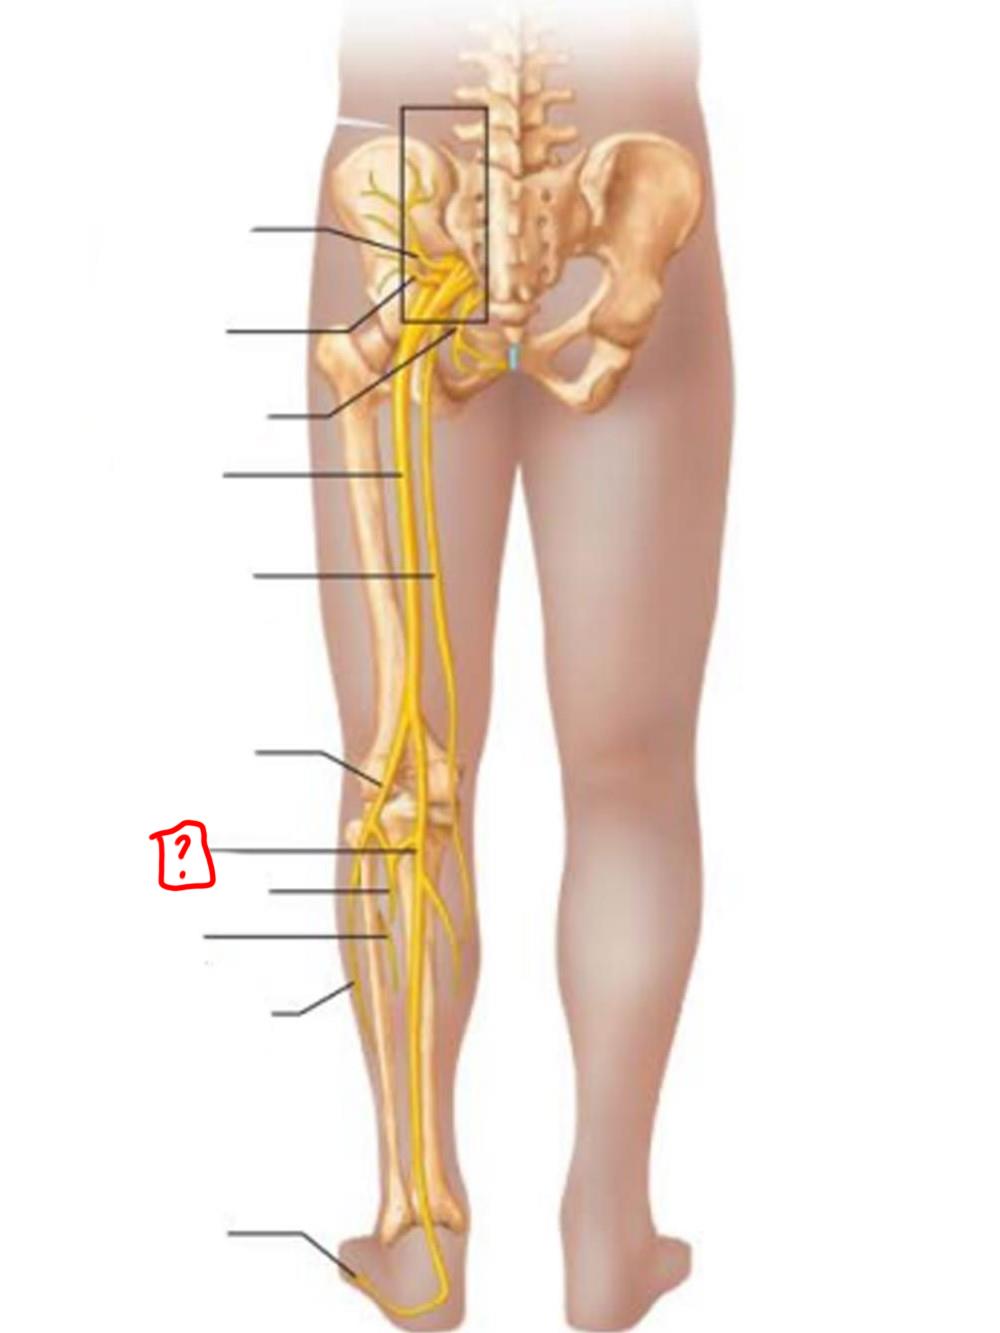

sciatic

posterior femoral cutaneous

common fibular

tibial nerve

sural (cut)

deep fibular

superficial fibular

plantar branches